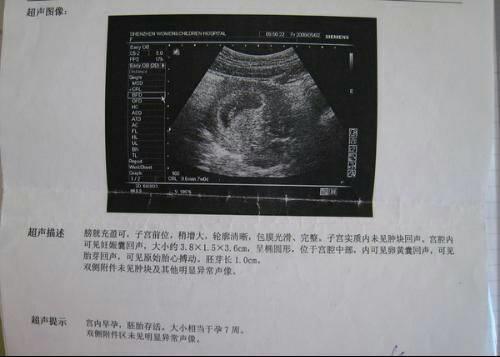

1、早孕b超单

在怀孕7周时,医生会建议你做个早孕b超,这个b超是看你是不是宫内孕。但是这b超单隐藏一个重要信息,可以帮你判断男女。

下图是孕囊的大小:数据相差大的生男孩,数据相差小的生女孩。如图3.8X1.5X3.6cm,有两个数值很接近,一个是他们的2倍的话可能是男孩。反之就是女宝。